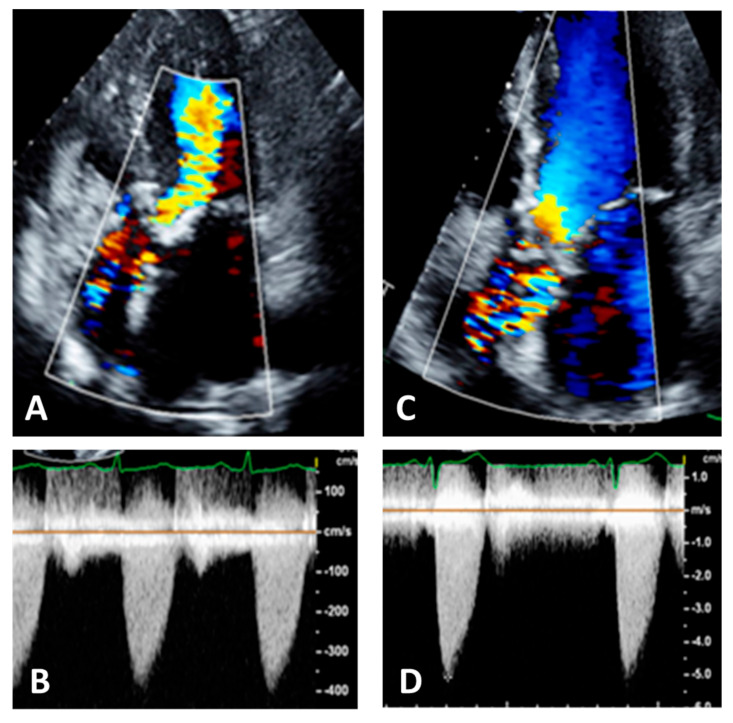

When measuring, it is important to search not only the highest velocities but also note which acoustic window yields this peak AS jet velocity [29,45]. Attention should be paid to identifying the highest velocity, i.e., aliasing, seen at color Doppler, not only at valve level but also in the ascending aorta so that the continuous beam should be placed as parallel as possible to this flow (Figure 9).

Figure 9.

Panel (A): five chamber view. Color Doppler is not well visualized in ascending aorta, Panel (B); this results in an underestimation of the aortic velocities. Panel (C): the same patient with correct visualization of color Doppler in ascending aorta, Panel (D). This results in an increase and correct recording of aortic velocities.